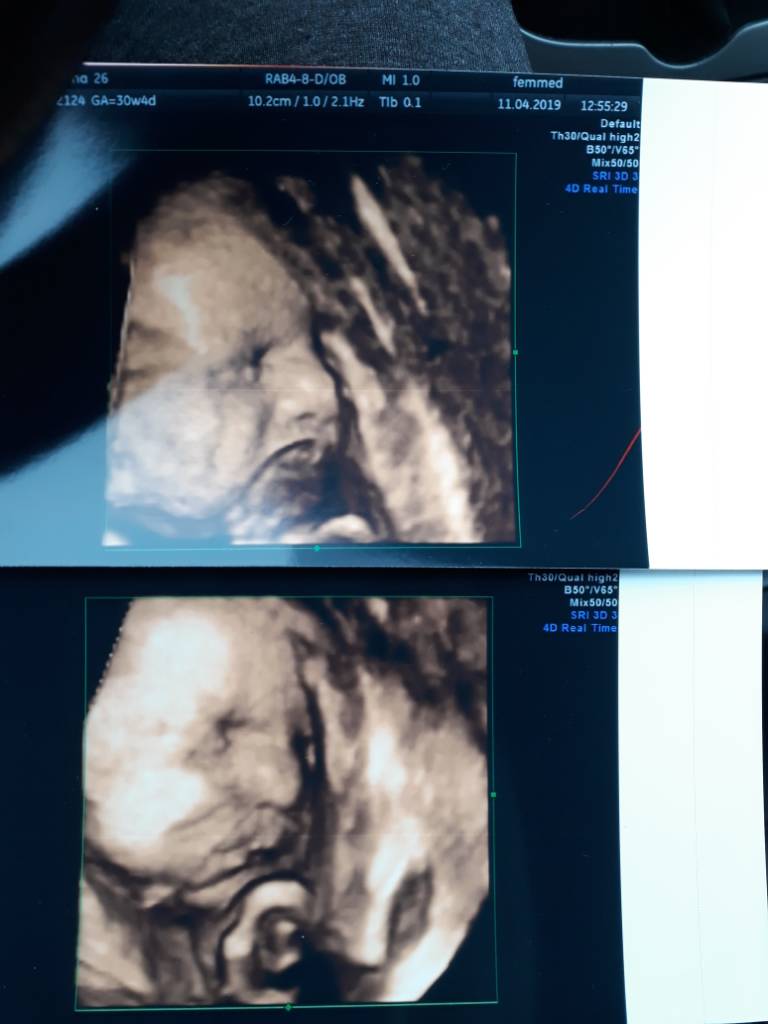

Ja wczoraj wizytowałam.

Waga ciężka u nas. 30+4 a "mała" 2020g. Z OM 16.06 a z USG 31.05...

Szyjka długa, twarda i zamknięta, także wszystko ok [emoji6]Zobacz załącznik 961629